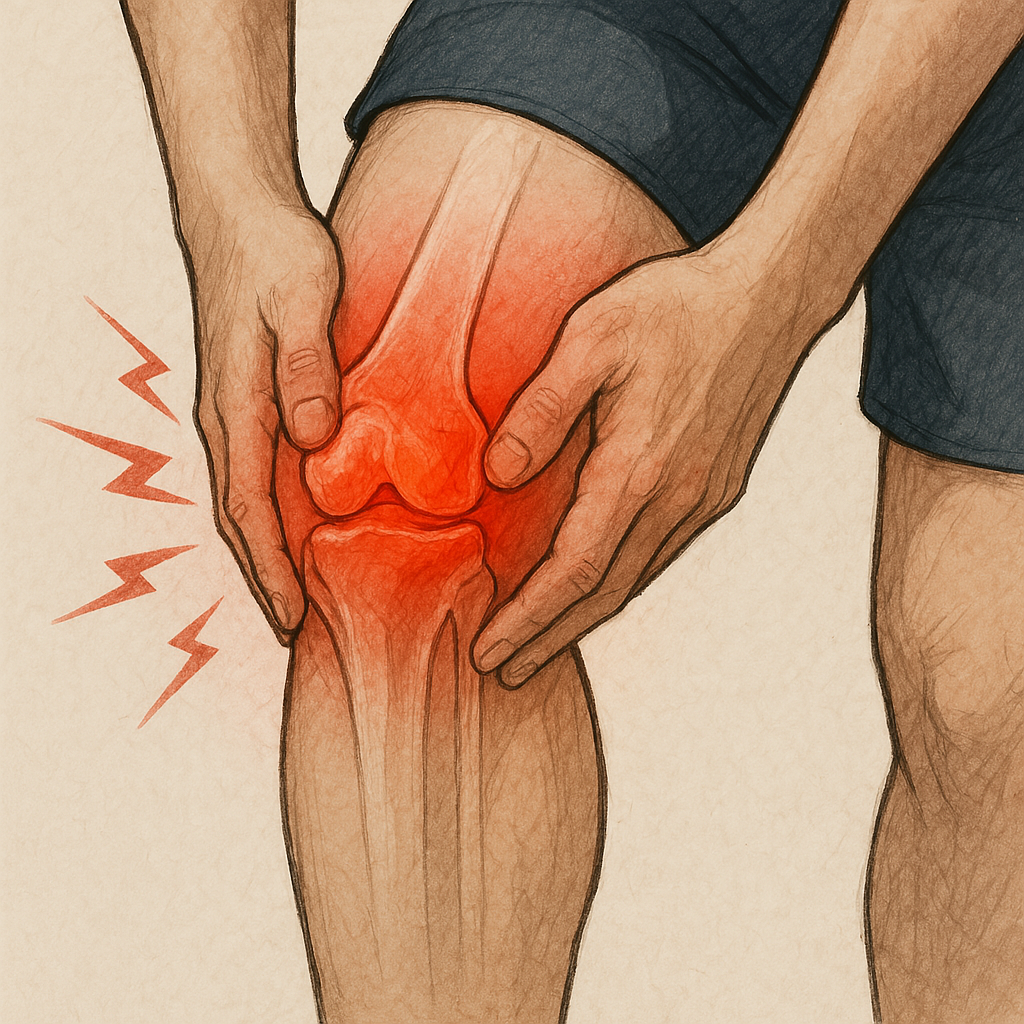

2025년 들어 중장년층을 중심으로 ‘관절 건강’에 대한 관심이 다시 높아지고 있습니다. 특히 퇴행성 관절염의 증가, 관절 통증으로 인한 일상 제한, 그리고 글루코사민·콘드로이친과 같은 보조 성분의 효과 재조명이 올해 건강 트렌드의 중요한 키워드로 떠오르고 있습니다.

그중 ‘콘드로이친’은 실제로 연골 보호와 통증 완화에 과학적 근거가 있는 대표 성분으로, 해외 가이드라인에서도 ‘권장 보충제’로 다시 복권되고 있습니다.

이번 글에서는 2025년 관절 건강 관리 트렌드를 중심으로 콘드로이친의 작용 원리, 복용법, 운동 요법까지 함께 정리해드립니다.